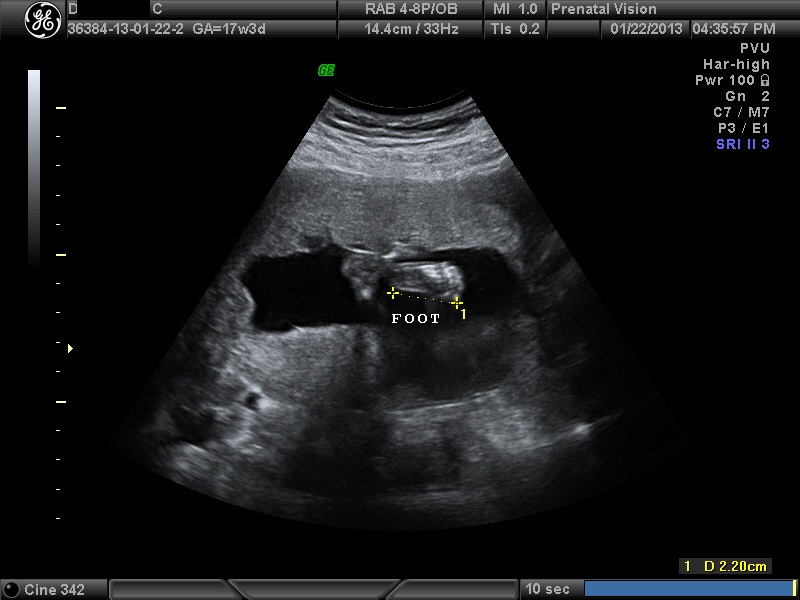

IMAGES_9 January 22, 2013 by Courtney Leave a comment ← Previous Image Next Image → 17w3d Like Loading...